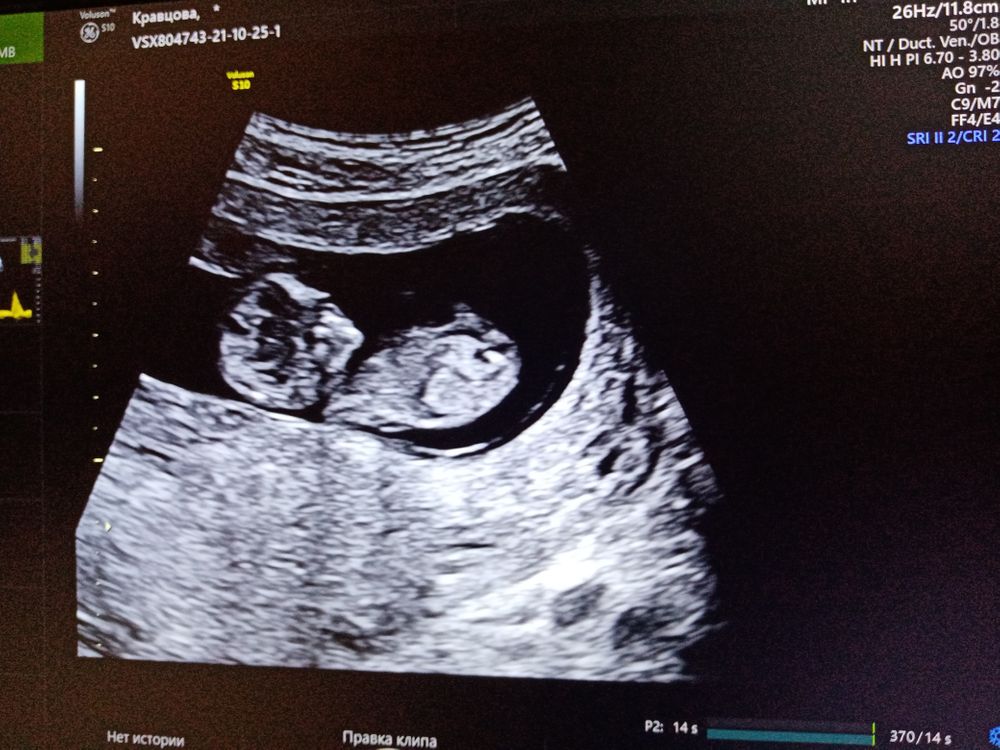

Пол на 1м скрининге

А я вижу мальчика

Видно не очень хорошо, но по-моему девочка.

Чашка утреннего кофе, а можете показать, где этот заветный бугорок?

Полина Анисимова, у вас малыш немного развёрнут, поэтому видно плохо. Предполагаю, что вот тут, но могу ошибаться. Изображение

Ракурс на фото не очень. Ребёночек как бы развернут немного анфас, а нужен точный профиль, чтобы хорошо разглядеть половой бугорок. Я, правда, увидела девочку, но это только предположение, не 100%.